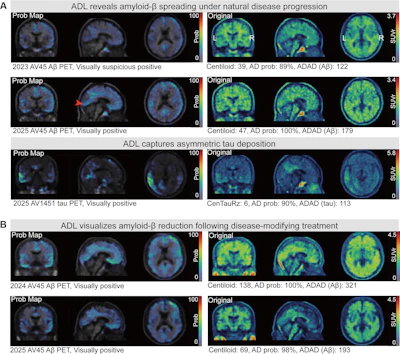

Adversarial decomposition learning (ADL) enables intuitive, longitudinal visualization of disease progression and treatment response, supporting clinician–artificial intelligence collaboration. (A) Images in a 48-year-old female patient who presented with mild cognitive impairment. The ADL probability maps highlighted occipital-temporal amyloid β (Aβ) spread and focal left-temporal tau pathologic abnormalities. An area of increased occipital AV45 uptake is shown (arrowhead). (B) Images in a 51-year-old male who presented with memory decline. For each image grid, the left side is the decoupler-output AD pathologic probability map, the upper right side is the original Aβ/tau PET image, and the lower right side is the image after AD component removal by the decoupler.Image and caption courtesy of RSNA.

Centiloid (CL) and CenTauRz (CTRz) can provide robust population-level anchors for biologic characterization, whereas ADAD may be more sensitive to clinically meaningful expression of disease in individual patients, they noted. A key finding from the study was that ADAD showed larger effect sizes with cognition and hippocampal volume than established scales in mixed-effects modeling, suggesting closer coupling to functional status and neurodegeneration, the authors wrote.

While established quantitative scales correlated more strongly with autopsy findings and cerebrospinal fluid (CSF) biomarkers, the AI-derived scoring tool still showed independent associations with cognitive decline and hippocampal volume loss over time, the group added.